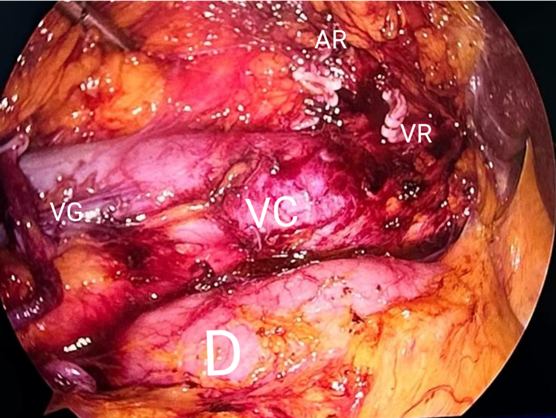

Por el riesgo de progresión tras el hallazgo de ambos tumores, siendo contralaterales y sincrónicos, se opta por realizar nefroureterectomía con rodete vesical del lado derecho (Imagen 3) y nefrectomía parcial izquierda, ambas por vía laparoscópica en un mismo tiempo quirúrgico (Imagen 4).

VG: vena gonadal, D: duodeno, VC: vena cava, AR: arteria renal, VR: vena renal.

Imagen 3 Lecho quirúrgico tras la nefroureterectomía derecha